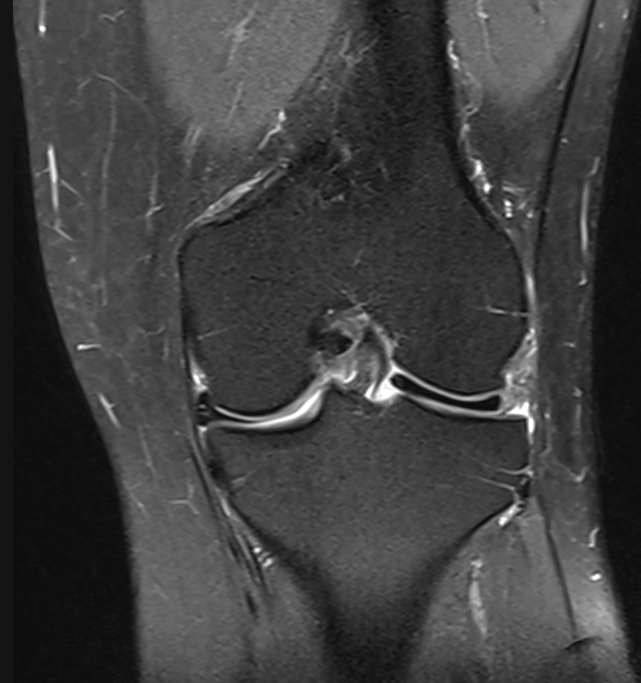

3. Discoid lateral meniscus